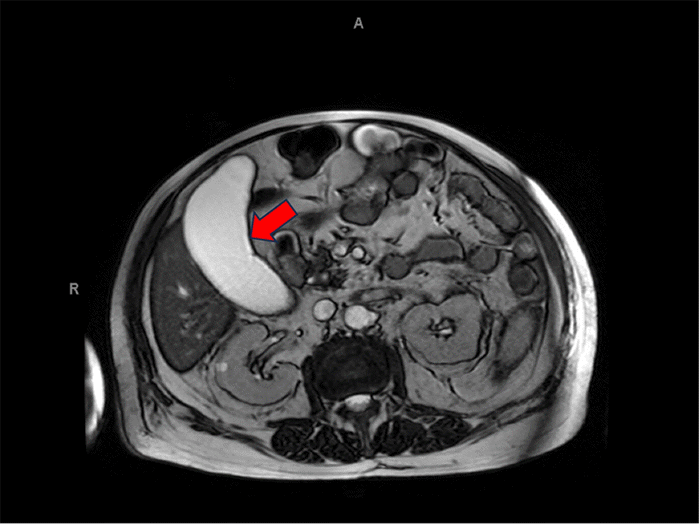

Figure 2. MRCP Demonstrating Gallbladder Hydrops. Published with Permission

MRCP image confirming marked gallbladder distension (hydrops, red arrow). The gallbladder measured approximately 13 cm in its maximum anterior-posterior dimension, and there was no evidence of biliary ductal obstruction

A 69-year-old male with a complex past medical history—notably including multiple myeloma, hypertension, insulin-dependent type 2 diabetes mellitus, and chronic obstructive pulmonary disease (COPD)—presented with a one-day history of severe right upper quadrant (RUQ) abdominal pain. This presentation occurred three weeks after a complicated hospital admission for anaplasmosis, Listeria monocytogenes and Pseudomonas aeruginosa bacteremia, during which he also experienced a cerebellar infarction and a provoked deep vein thrombosis (DVT) of the right upper extremity, necessitating anticoagulation with apixaban. Importantly, imaging during that prior admission (CT and MRCP) had revealed gallbladder hydrops (13 cm distension) without evidence of acute cholecystitis or ductal obstruction (Figures 1 and 2), for which no specific biliary intervention was undertaken at that time.